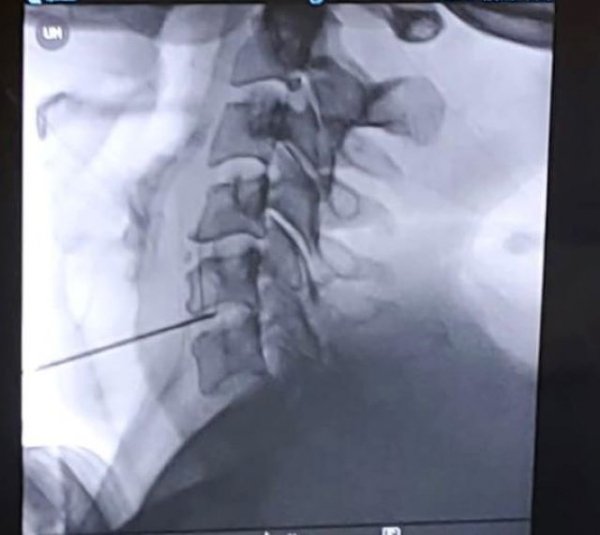

Con este nuevo sistema, que se está aplicando ya en el Hospital Universitario y Politécnico de La Fe, en Valencia, se accede al disco cervical dañado mediante una aguja que aplica directamente radiofrecuencia que hace que el disco se retraiga hasta su posición habitual y se pueda corregir la hernia a tratar.

Esta nueva técnica fue presentada en el centro hospitalario mediante una intervención de demostración desarrollada hace unos días por uno de los especialistas en Anestesiología responsables de esta Unidad del Dolor Rafael Omaña y que se aplicó a una paciente con hernia discal cervical.

El anestesiólogo y responsable de la aplicación de esta técnica en el Hospital Universitario de La Palma, Rafael Omaña, asegura que “es un nuevo tratamiento de descompresión discal percutánea mediante radiofrecuencia coablativa que reduce el dolor causado por una protrusión o hernia discal cervical contenida”. Además, destaca que se trata de un procedimiento ambulatorio que no requiere cirugía y que aporta una notable mejoría clínica a los pacientes que pueden recuperar su actividad habitual sin secuelas.